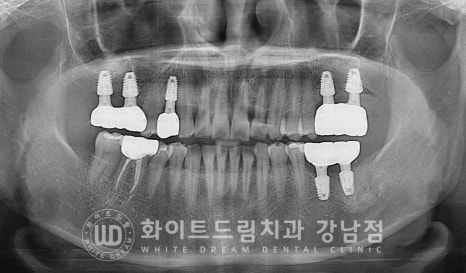

▲ 상악동 거상술 & 임플란트 수술 후 (23.03.07)

상/하악으로 나누어 수술을 진행하는 것보다

오른쪽, 왼쪽으로 나누어 수술을 진행하는 것이

환자분이 식사하기 더 편하실 것으로 판단되어

2회로 나누어 임플란트 식립을 진행하였습니다.

오른쪽 상악 : 23.03.07 / 왼쪽 상, 하악 : 23.03.20

많은 양의 뼈이식이 동반되었기에

충분히 임플란트가 유착될 수 있도록 회복 기간을 넉넉히 잡기로 했습니다.

환자분은 수술 후 5개월의 회복 기간을 가진 후

임플란트 보철 제작 & 세팅에 들어가게 되었습니다.

식립된 임플란트들이 상실된 치아의 기능을 정상적으로 이행함을 확인하며

치료를 마무리하게 되었습니다.